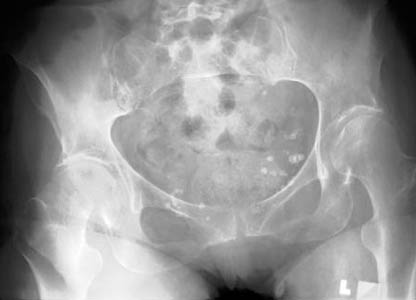

Look at the following radiograph and try to identify the fracture. Can you find it?

Click on the image for the answer.

AP view of pelvis